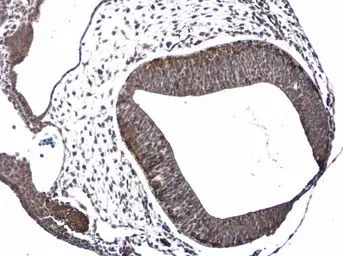

Anti-Doublecortin antibody used in IHC (Paraffin sections) (IHC-P). GTX134052

GTX134052 IHC-P Image

The data was published in the journal Int J Mol Sci in 2020.PMID: 32046281